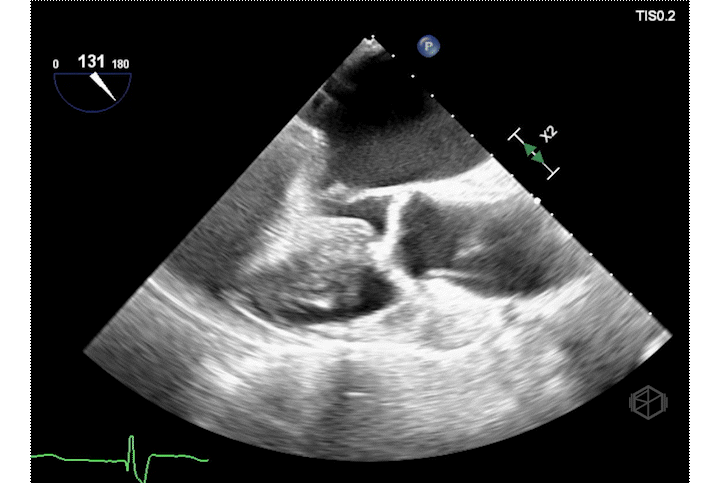

There is something moving within the aortic root, a flap like structure, and there is a mixed echogenicity pericardial effusion. The patient had a stat CT surgery consult and rushed for a stat CTA and that demonstrated “acute Stanford type A aortic dissection. An intimal flap appears to extend down to the aortic root just above the level of the right coronary artery which is patent and emanates from the true lumen. Moderate hemopericardium in the pericardial space as well as in the pericardial recess where it also surrounds the pulmonary artery.” The patient was taken by CT surgery for emergent repair.

Intra-operative TEE showing the dissection flap.